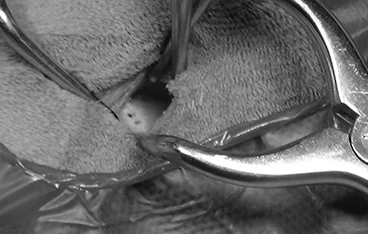

외이도 종괴, 외이염&중이염&내이염

TECA+LBO / VBO

• TECA+LBO 수술 전

TECA+LBO 수술 후